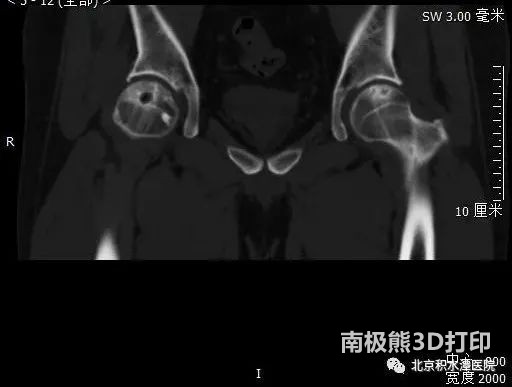

▲术前股骨头塌陷区个性化建模及定制化假体方案效果

杨德金副主任医师选定通过安全外科脱位入路(SSD入路)开展手术。通过术中细致的显露,保留了供养股骨头的主要血管、股骨头正常软骨及盂唇等重要结构。术中发现患者股骨头负重区已塌陷,而塌陷区周边骨质及软骨面完好,印证了术前判断。通过术中相应器械的精准定位,塌陷区组织被精准切除。定制化假体植入后,稳定牢固,其表面与股骨头正常软骨面实现了平滑的过渡。手术过程顺利、流畅,术后患者关节活动度恢复正常。术后影像学检查显示定制化假体大小完美契合原坏死塌陷区大小,健康骨质得以保留。

▲术后影像学显示定制化假体大小完美契合原坏死塌陷区大小,健康骨质得以保留,同时假体表面与正常股骨头骨面过渡平滑。